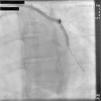

A 67-year-old woman with a history of coronary artery bypass grafting (CABG) six months previously underwent coronary angiography for stable class III angina. Extensive thrombus burden was visualized in the mid-distal segment of the saphenous vein graft (SVG) to the second obtuse marginal branch with decreased Thrombolysis In Myocardial Infarction (TIMI) 2 flow (Figures 1 and 2) and without evidence of obstructive atherosclerosis. The patient was placed on oral anticoagulation with rivaroxaban (Janssen Pharmaceuticals, Titusville, NJ, USA) 20 mg once daily. Follow-up catheterization after four weeks revealed angiographic resolution of the thrombus with significantly improved TIMI 3 flow (Figures 3 and 4).